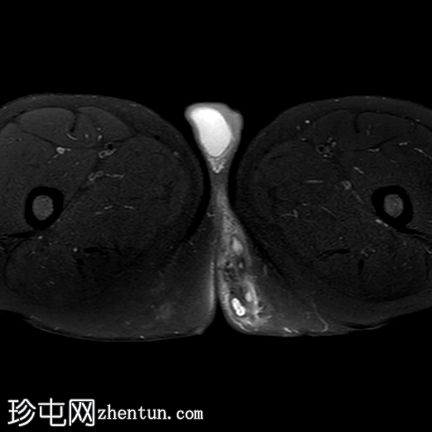

轴位PD加权像

脂肪抑制像

一条低T1信号、高T2/PD信号的弧形瘘管连接肛门黏膜和左侧会阴皮肤,并伴有明显的管状强化。该瘘管从肛门黏膜后方6点钟方向穿过肛门内括约肌,然后穿过括约肌间隙,但未穿过肛门外括约肌。皮下少量积液提示脓肿形成。上述影像学表现符合2级括约肌间肛周瘘。

根据圣詹姆斯大学医院的分类,这是一例活动性 2 级括约肌间肛周瘘 1 型病例。